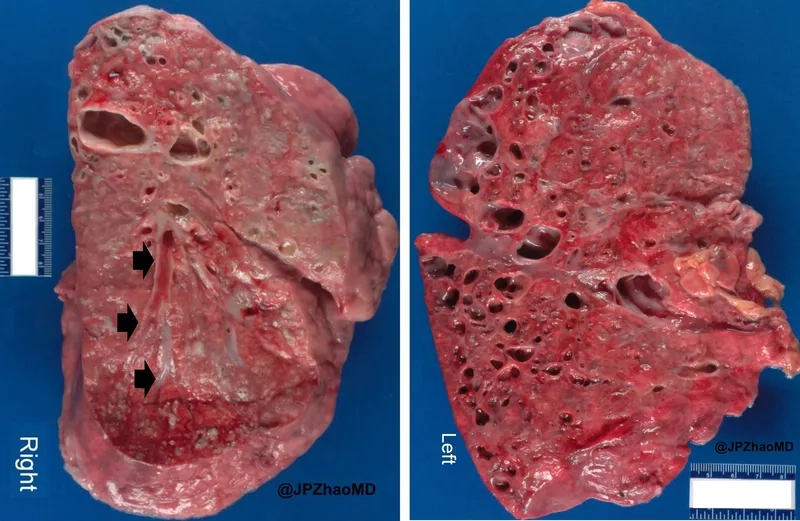

Diagram of lungs with Bronchiectasis